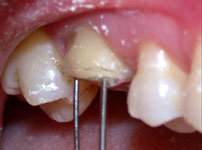

Fig. 7

Fios ortodônticos de 0.7 mm inseridos nos orifícios permitindo a visualização do paralelismo ou não após a realização das perfurações.

Para conseguir o paralelismo entre os orifícios, um fio ortodôntico foi inserido na primeira perfuração, o que auxiliava no posicionamento paralelo da broca no momento da realização do segundo orifício e, assim sucessivamente, até a última perfuração (Fig. 7).